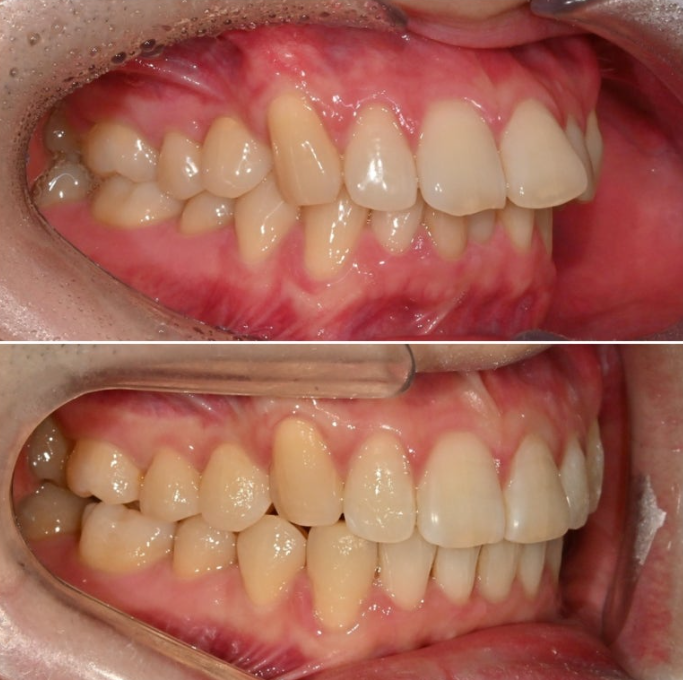

25.02

올해 초, 교정치료를 위해 내원한 30대 후반의 환자분입니다.

앞니가 깊게 물리는 과개교합.

중심선 불일치. 정도가 보입니다.

앞니가 많이 뻗쳐있습니다.

위 앞니 뻗침이 심하면 위 아래 앞니 사이 간극이 커지죠.

위아래 어금니 물리는 교합관계는 그래도 1급에 가깝습니다.

악궁모양이 약간 찌그러진 형태입니다.

25년 2월부터 6월까지 14개 첫세트 장치를 모두 낀 후 모습입니다.

과개교합은 대부분 개선되었고 중심선 불일치도 개선되었습니다.